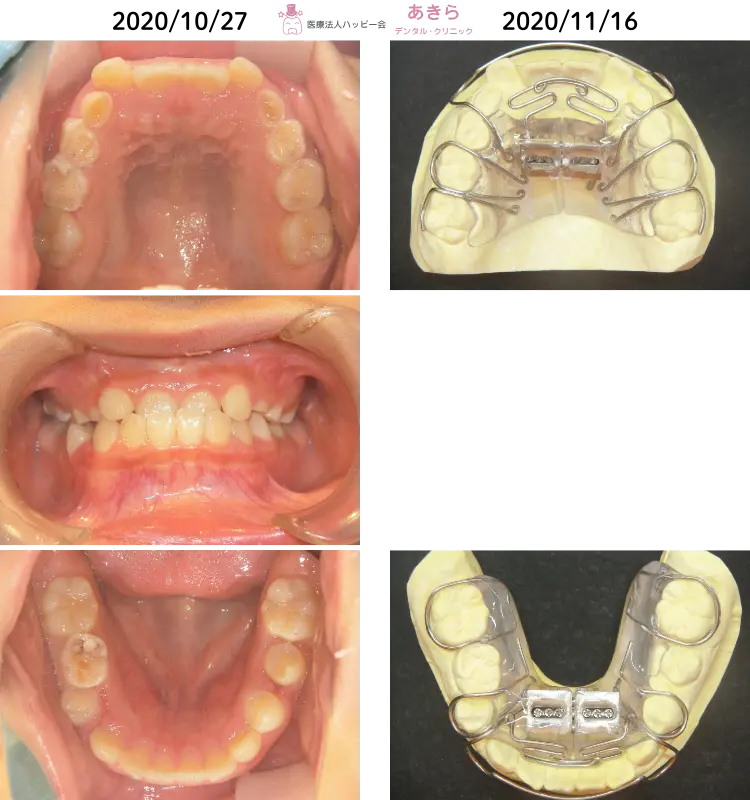

2020年10月27日 初診時 ⇒ 11月16日 SHAスタート時